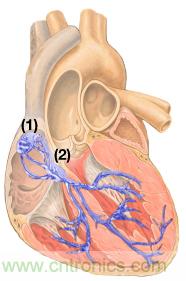

心臟作為一種生化機(jī)電系統(tǒng),會(huì)產(chǎn)生電脈沖,從右上心房的 竇房結(jié)(SA)傳導(dǎo)至房室結(jié)(AV)。竇房結(jié)節(jié)充當(dāng)作該系統(tǒng)的起搏器(圖1)。

圖1. 心肌與竇房結(jié)(1)和房室結(jié)(2)11